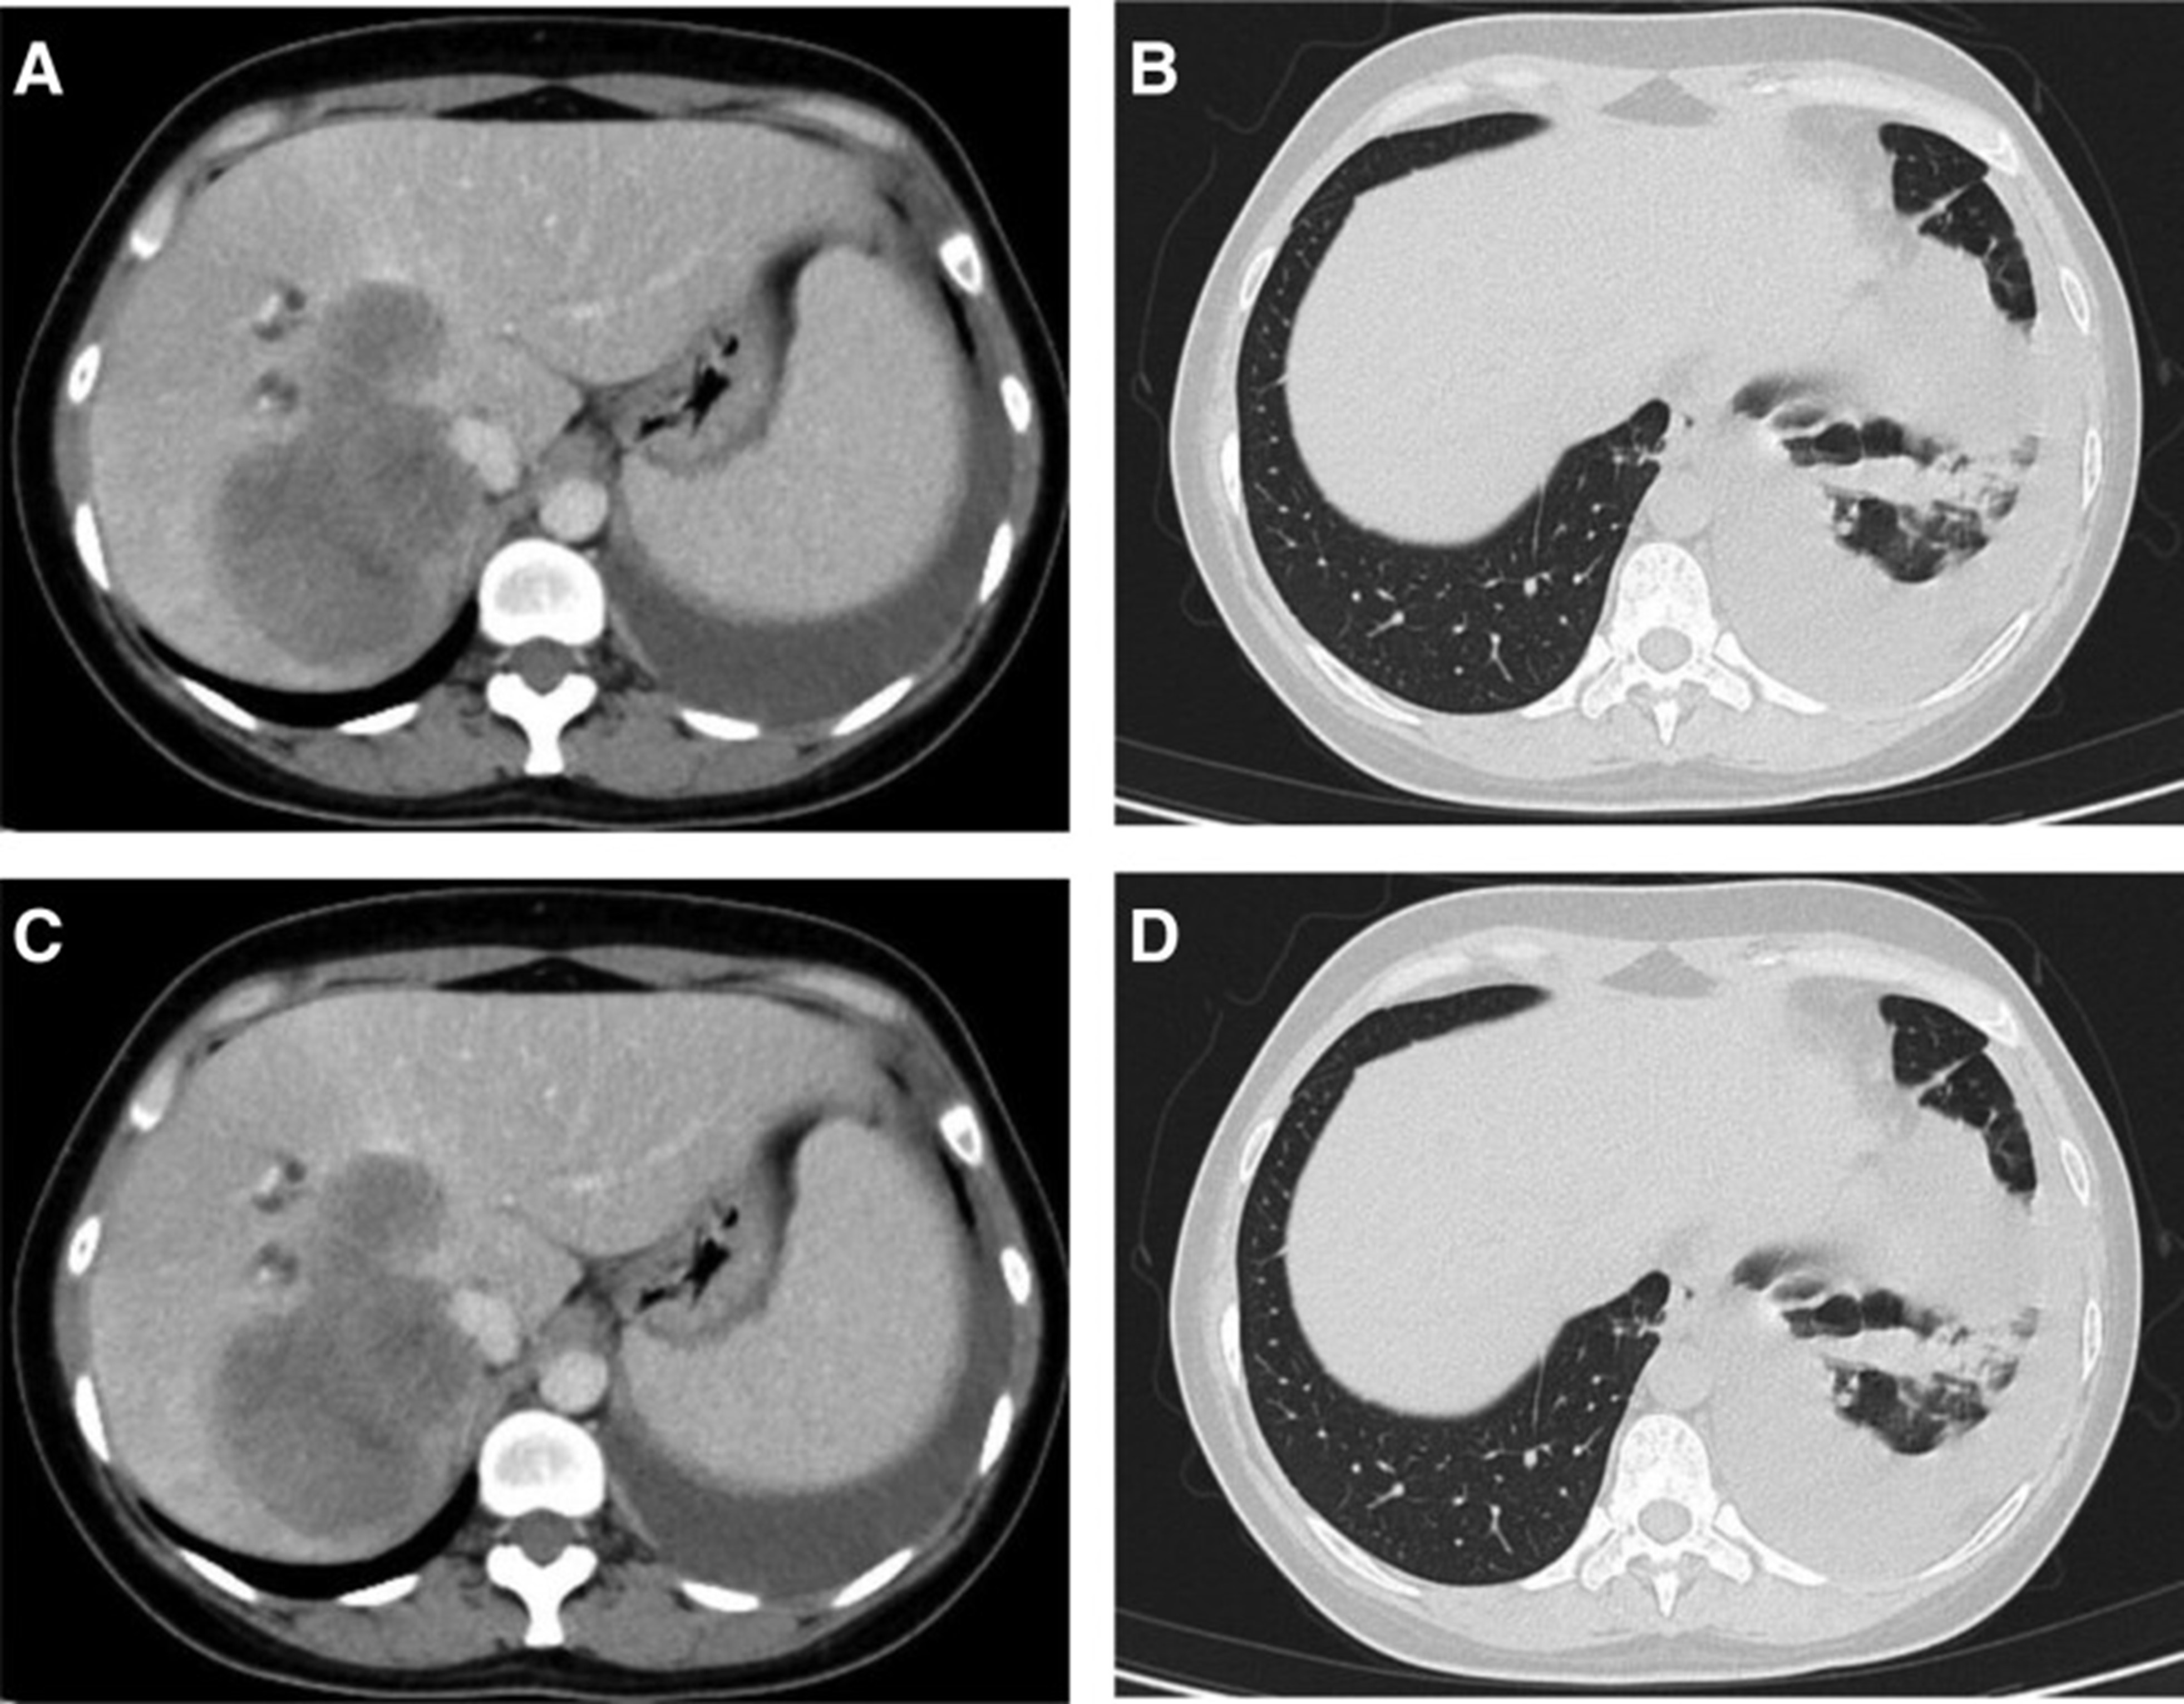

2020年4月,患者胸部CT示“双肺多发结节,纵隔及肺门多发肿大淋巴结;附着于肝右叶,略呈低密度肿块影”(图 1)。(图4A,4A、B)和腹部CT显示“肝脏多发肿块”(图1)。(图 4C)。骨扫描显示“身体多个部位的骨代谢异常增强”。2020年4月19日,对“右肝肿块和右锁骨上肿块”进行活检,病理指征(右肝肿块抽吸、右锁骨上肿块抽吸)为低分化腺癌。结合免疫组化结果,首先考虑的是肺腺癌转移。最终诊断为“IV期肺腺癌伴多发肝和骨转移”。基因检测显示“EML 4-ALK 融合,PD-L1 肿瘤阳性细胞数TPS 80%”(图 2)。(图1和和2)。

图 4:2020 年 4 月 (A-C) 和 2020 年 6 月 (D-F) 的 CT 扫描。CT = 计算机断层扫描。

2020年5月1日,患者开始口服艾乐替尼靶向药物进行治疗,2020年6月25日复查,确定治疗效果为PR(部分有效)(根据RECIST1.1)显示肺病灶和肝转移灶明显减少(图1)。(图 3D-F)。2020 年 8 月 27 日复查确定治疗效果为疾病进展(PD, progressive disease),根据 RECIST1.1显示肝脏病变变大(图 1)(图 4A-D)。进行了第二次肝活检,随后的病理学显示“(肝)低分化癌,结合免疫组织化学分析考虑肺腺癌转移”。组织活检进行了第二轮基因检测,结果显示“BRAFV600E 14.79%,EML 4-ALK fusion 14.47%”(图 1)(图 5)。2020年9月20日,对患者我以为用恩沙替尼联合达拉非尼靶向治疗。治疗开始后,患者出现明显发热、寒战、乏力和厌食。期间患者左侧出现大量胸腔积液,胸腔积液中脱落细胞为“非典型细胞,考虑为腺癌”。随后,该患者接受了 1 次胸腔内铂输注。

图 5:2020 年 6 月(A 和 B)和 2020 年 8 月(C 和 D)的 CT 扫描。CT = 计算机断层扫描。